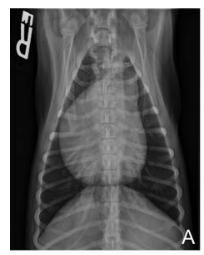

Which is considered a less likely differential for this cardiac appearance?

a) heartworm

b) pulmonic stenosis

c) mitral valve disease

d) pulmonary hypertension

A

Reverse D shape (right ventricular enlargement) less likely due to

however can occur due to severe LA and LV enlargement due to morphological distortion of cardiac anatomy